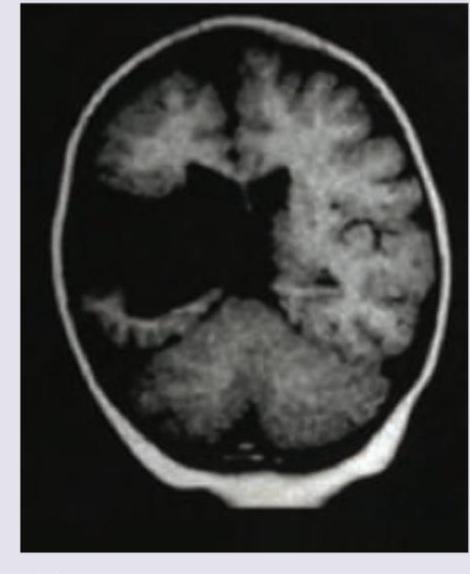

Question 4: A 2-year-old epileptic child with developmental delay presents to emergency with fever for the last two days. NCCT shows:

- D. Lissencephaly (Correct Answer)

Explanation: ***Lissencephaly*** - The image shows a **smooth brain surface** with **absent or reduced gyri and sulci**, which is characteristic of lissencephaly. - This condition is often associated with **developmental delay** and **epilepsy**, consistent with the child's presentation. *Subdural hemorrhage* - A subdural hemorrhage would appear as a **crescent-shaped collection of blood** between the dura mater and arachnoid mater. - The image does not demonstrate any such blood collection. *Arnold-Chiari malformation* - Arnold-Chiari malformation involves the downward displacement of the **cerebellar tonsils** into the foramen magnum. - While it can cause neurological symptoms, the primary finding in the image is a smooth cerebral cortex, not cerebellar displacement. *Schizencephaly* - Schizencephaly is characterized by **clefts or slits in the cerebral hemispheres** that extend from the pial surface to the ventricles. - The image shows a smooth brain surface rather than distinct full-thickness clefts.